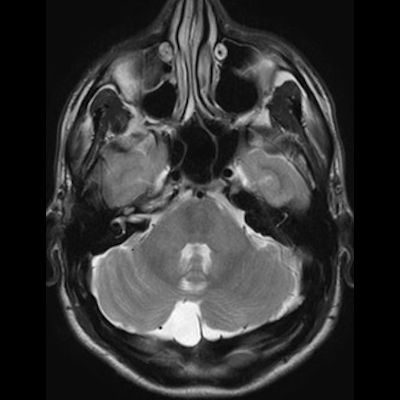

11 ay, Nöbet

Charlevoix-Saguenay Otozomal Resesif Spastik Ataksisi (ARSACS)

Charlevoix-Saguenay Otozomal Resesif Spastik Ataksisi ARSACS

ARSACS (Charlevoix-Saguenay otozomal resesif spastik ataksisi) Sendromu

Serebellar folya sinapsisi